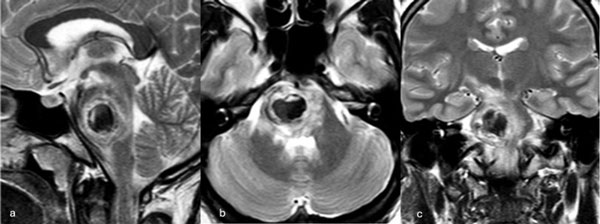

Figura 3. RM preoperatoria de encéfalo. Se evidencia una lesión única intraaxial centrada en puente y pedúnculo cerebeloso derecho, sugerente de un cavernoma roto. A, B y C) Imágenes ponderadas en T2 en cortes sagital, axial y coronal, respectivamente, donde se observa un importante hiperintensidad perilesional, sugerente de edema.

Caso 2: cavernoma pontino

Una paciente femenina de 28 años, sin antecedentes de sangrado previo, debutó con cefalea, náuseas y vómitos, asociado a diplopía secundaria a una parálisis del VI par derecho. La RM de encéfalo evidenció una malformación cavernomatosa centrada en puente y el pedúnculo cerebeloso medio derecho (Figura 3). Un mes después del sangrado, se realizó una exéresis de la lesión mediante un abordaje retrosigmoideo ampliado a través del pedúnculo cerebeloso medio (Figura 4), logrando una exéresis completa (Figura 5). Tras el procedimiento, la paciente evolucionó con hemihipoestesia del hemicuerpo izquierdo, sin otros síntomas agregados.